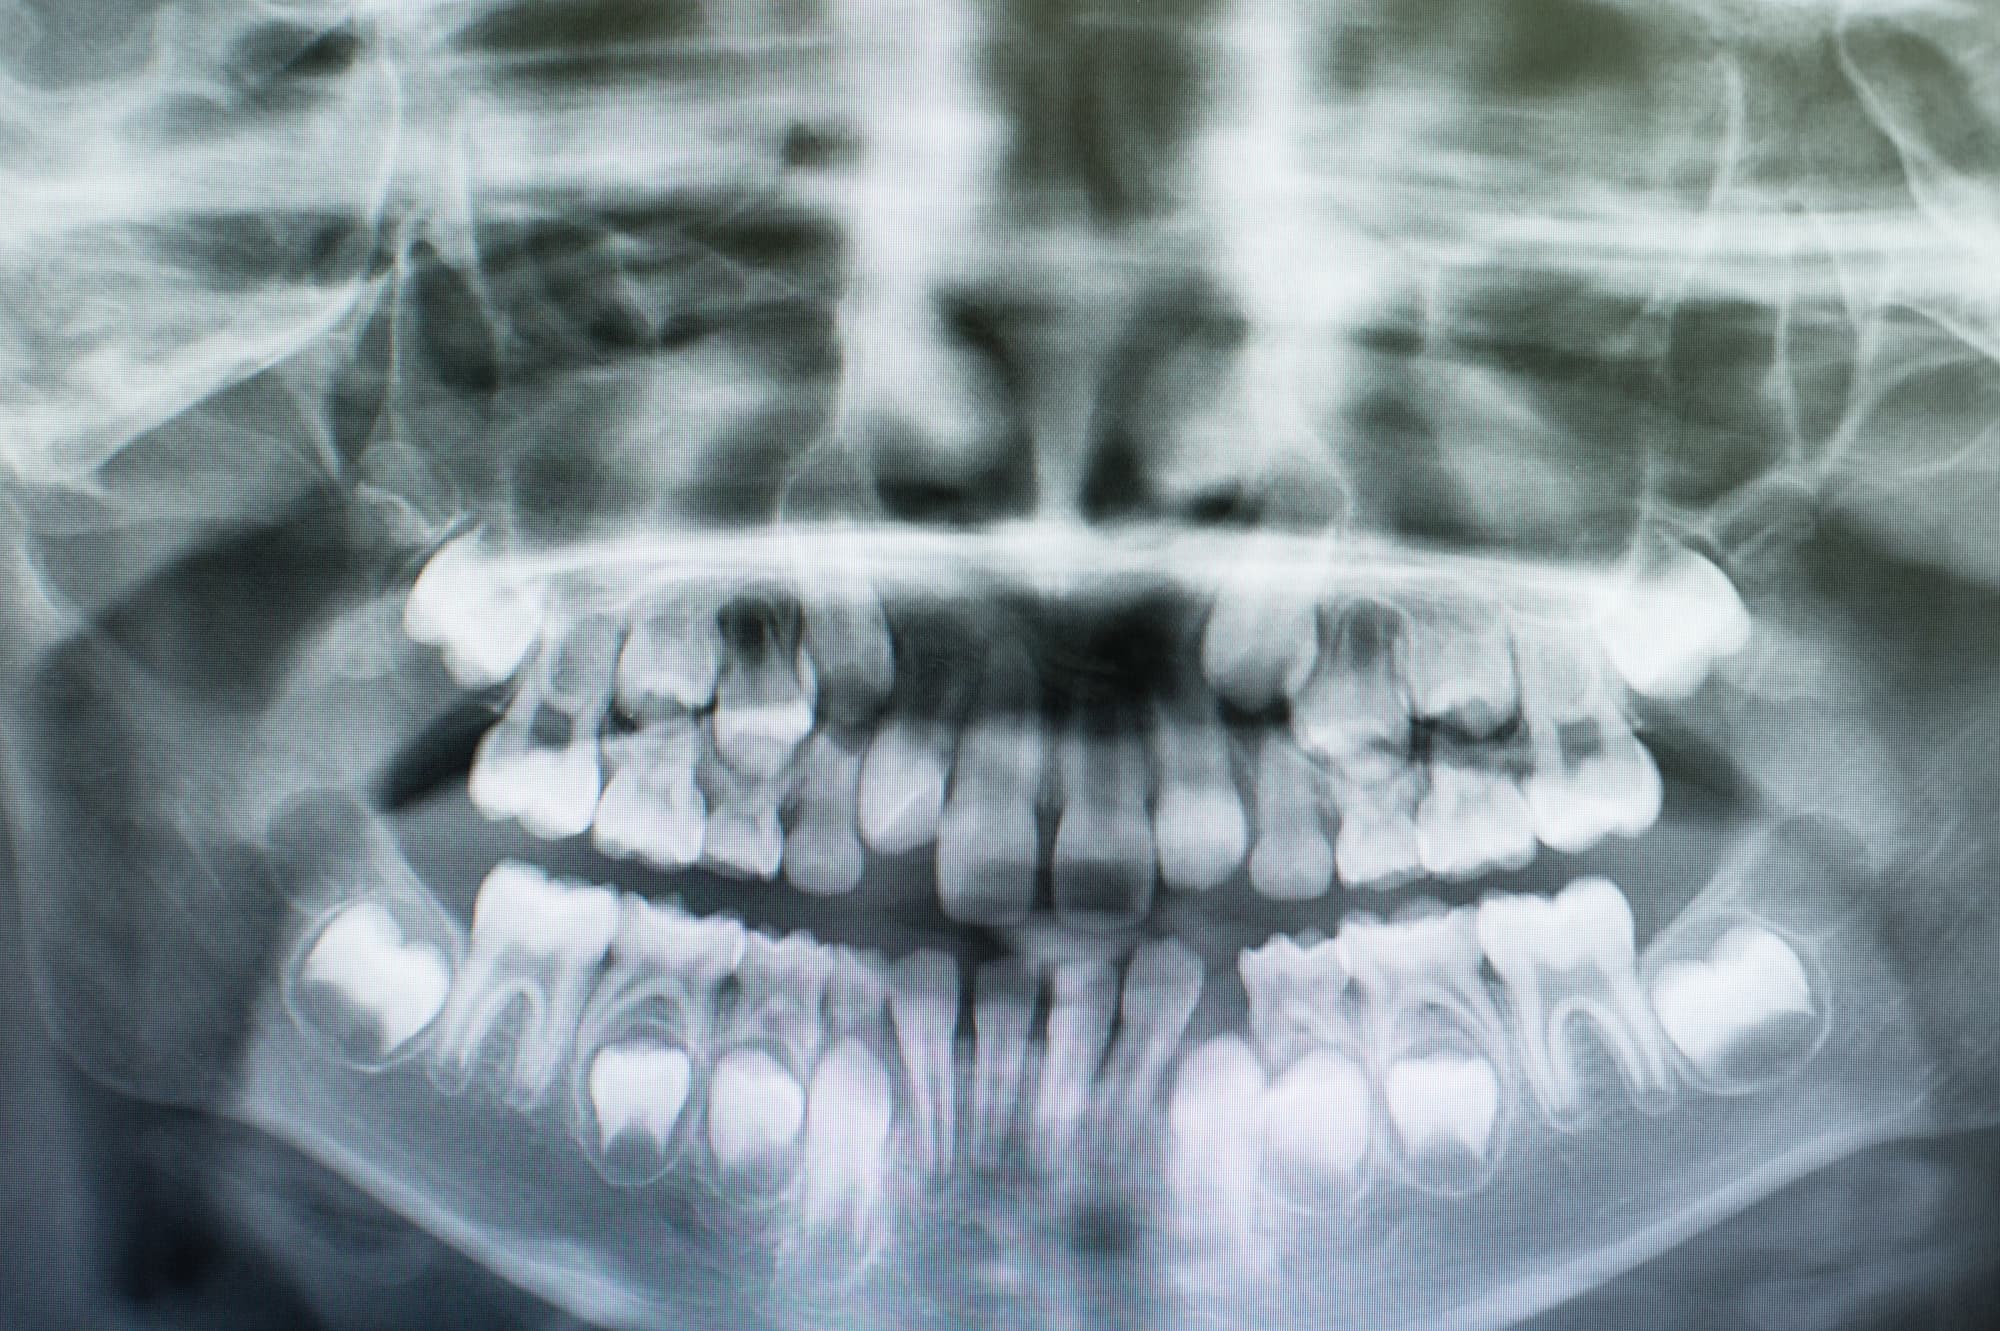

叢生(そうせい)とは、歯が本来の位置にきれいに並ばず、デコボコに重なり合って生えている状態をいいます。これは、顎の大きさに対して歯が並ぶスペースが足りない場合に起こりやすく、歯がねじれたり前後にずれたりして歯列全体のバランスが崩れます。

特に永久歯への生え変わり時期に多く見られ、見た目の問題だけでなく、清掃が行き届かなくなることで虫歯や歯周病のリスクが高くなります。

叢生があると歯磨きが難しくなり、食べかすや歯垢がたまりやすくなるため、口臭や歯肉の炎症を引き起こす原因にもなります。また、噛み合わせのバランスが崩れることで、顎の関節や筋肉に余分な負担がかかり、将来的に顎関節症を引き起こすこともあります。

気になる歯の重なりが見られた場合は、早めに歯科医院で診断を受け、適切な対応を検討することが大切です。